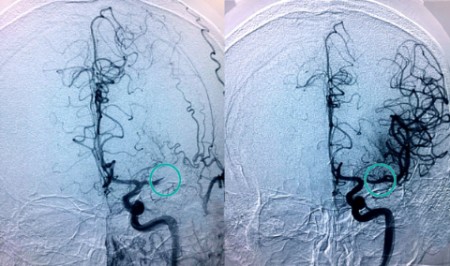

"Cuando una arteria del cerebro se obstruye se dispone de una ventana de muy poco tiempo para recanalizarla", explica el doctor Jaime González Valcárcel, neurólogo coordinador de la Unidad de Ictus del Complejo Hospitalario Ruber Juan Bravo. "Cada minuto cuenta en la fase aguda del ictus. Sabemos que por cada 15 minutos que se adelanta la primera intervención en caso de ictus disminuye un 4 por ciento el riesgo de discapacidad y también en un 4 por ciento la mortalidad".

. "El neurólogo de guardia del Complejo Hospitalario Ruber Juan Bravo puede acceder en tiempo real a la exploración del paciente y a sus pruebas del resto de centros, pudiendo ser tratado el paciente en un primer momento o trasladarlo para ser intervenido y extraer el trombo si fuera necesario", detalla el doctor Rafael Arroyo.